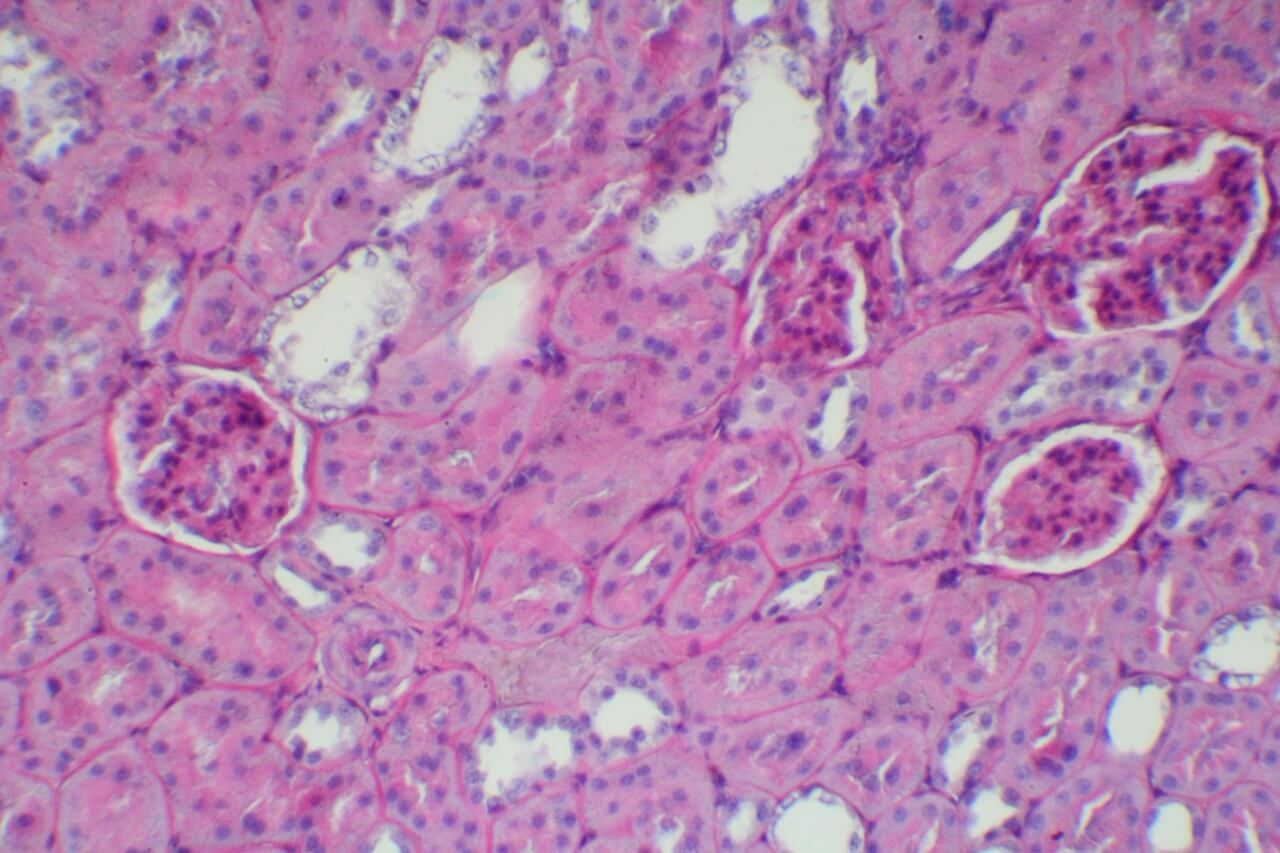

HE染色